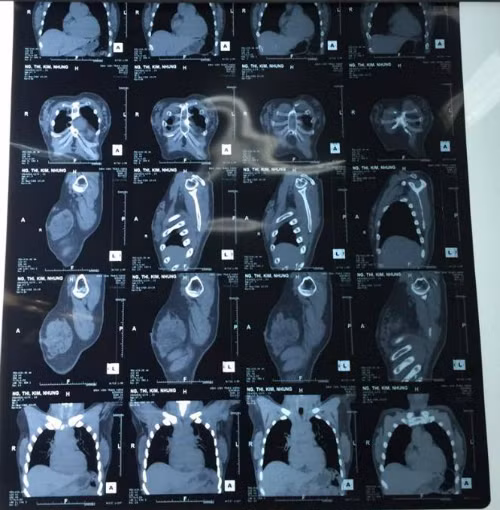

Kết quả CT Scan.

Vùng ngực có nhiều khối u chắc, kích thước đa dạng và rải rác khắp tuyến vú hai bên. CT Scan cho thấy nhiều nốt cản quang nằm rải rác ở mô mỡ và mô tuyến vú.